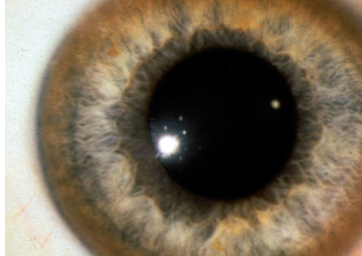

Case 9

A 26 years old female presented with dystonia. O/E is found to have ascites due to portal hypertension & asymptomatic golden brown rings around the corneo-scleral junction (limbus) of the eyes as shown

-

What you see in Pic ? Kayser Fleischer

Diagnosis?: Wilson’s Disease